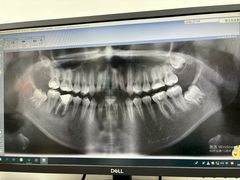

• -上海市青浦区中医医院

匿名用户 | 24-12-06